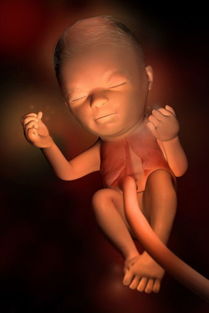

20周胎儿系统B超检查主要包括以下几个方面:

头部:观察胎儿头部的大小、形态,排除脑积水、小头畸形等。

面部:检查胎儿嘴唇、鼻骨等面部结构,排除唇裂、腭裂等畸形。

脊柱:观察胎儿脊柱的连续性,排除脊柱裂等畸形。

四肢:检查胎儿四肢的长度、形态,排除四肢畸形。

心脏:观察胎儿心脏的大小、形态,排除心脏畸形。

腹部:检查胎儿胃泡、胆囊、双肾、膀胱等腹部器官,排除相关畸形。

胎盘:观察胎盘的位置、形态,评估胎盘功能。

羊水:检查羊水的量,排除羊水过多或过少。